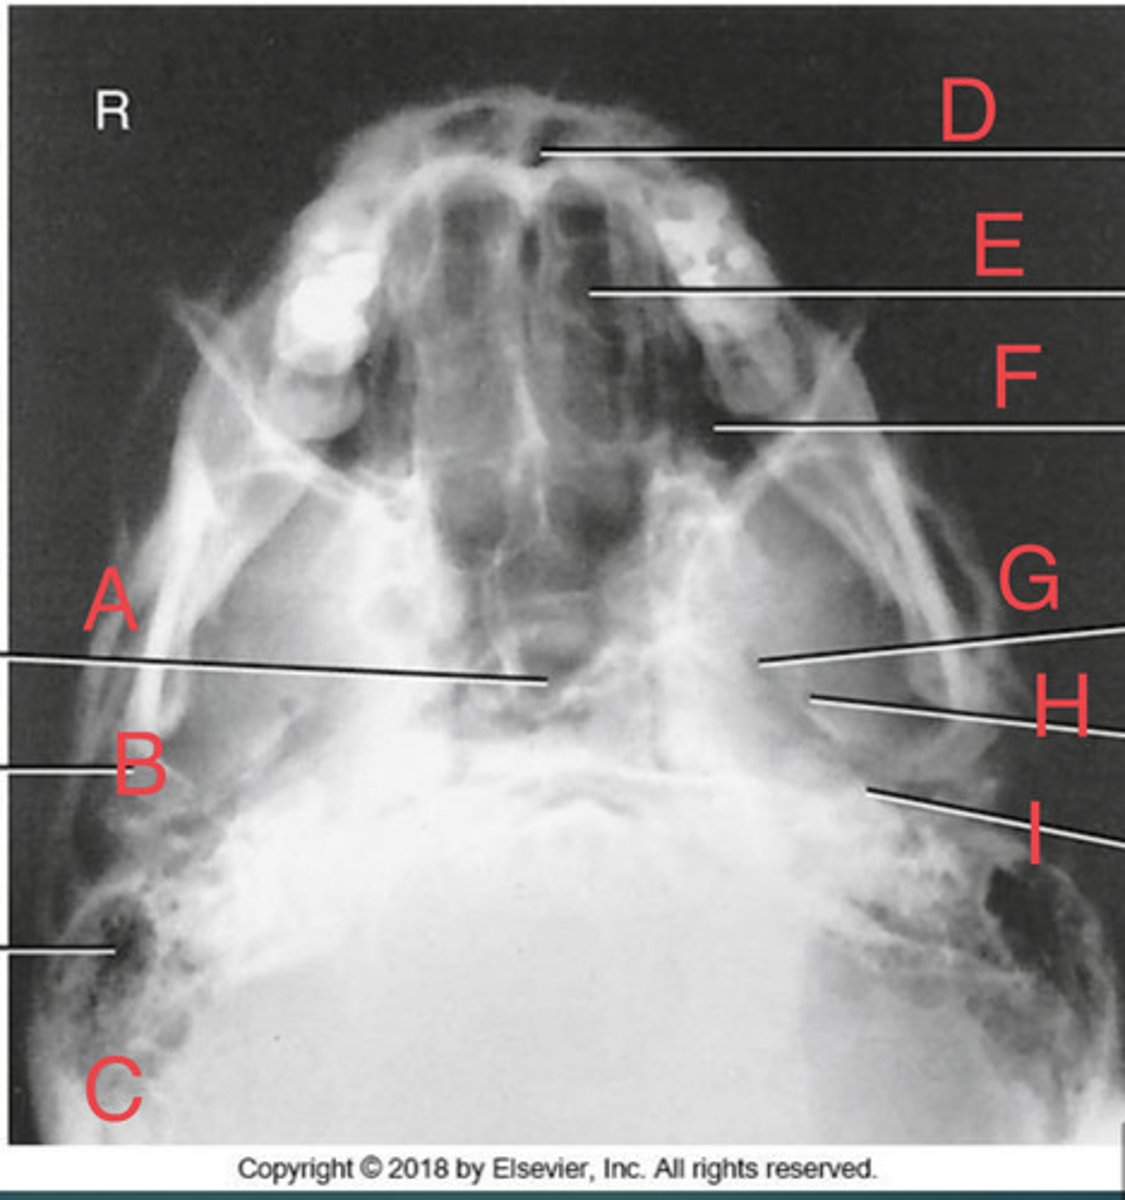

SMV sinuses

What position?

Sphenoid sinus of sphenoid bone

A.

R mandibular condyle of mandible

B.

R Mastoid air cells of temporal bone

C.

Nasal fossa

D.

L. Ethmoid sinus of ethmoid bone

E.

L maxillary sinus of maxilla

F.

L foramen ovale of sphenoid bone

G.

foramen spinosum of sphenoid bone

H.